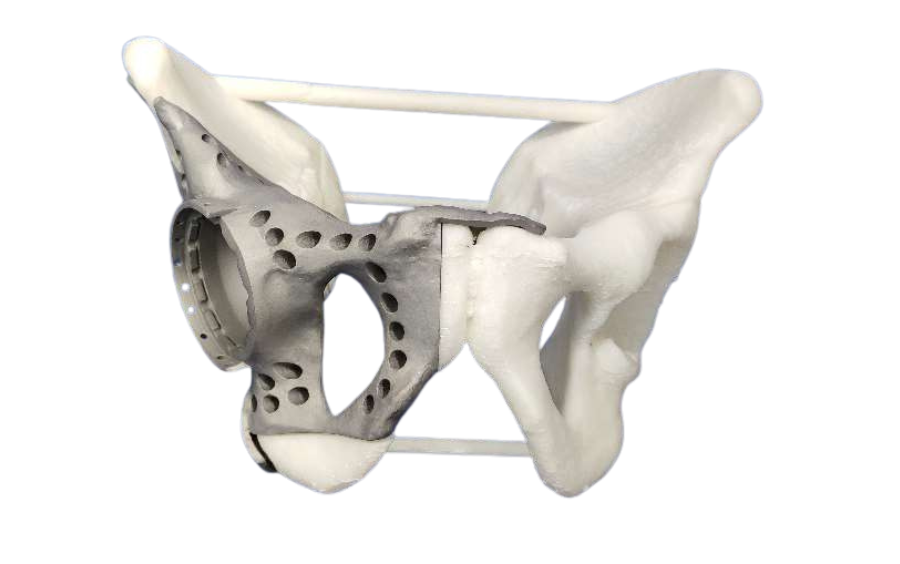

Dr. Himanshu Rohela leading Onco Orthopedic surgeon in Mumbai, Maharashtra after studying the scan and his previous treatment records, concluded that the patient is suffering from cancer of right pelvic bone having tumor. The challenge was to save the leg thus using Patient Specific Cutting Guides and Patient Specific Hip implant. Incredible team discussed with Dr. Rohela, the designing and entire manufacturing process. It initially started with surgical planning and case simulation with the help of US FDA & CE approved Materialise Mimics software by superimposing CT & MRI DICOM data & Anatomical Model. As Anatomical model maintained 1:1 ratio with the anatomy, hence showed excellent detailing of the defect, the model was also used to design jigs & implant on actual bone, which further helped the pre surgical planning. Once the planning was finalized, the surgery was accompanied with not only Customized Implant but also Cutting guides & Jigs. Read more

Implant was manufactured under ISO 13485 guidelines & tested to give an accurate fit & utmost safety.

Cutting Guides and Jigs from 3D Incredible helped the Surgeon to give an accurate cut and complete the surgery in one go. Once the resection was done, customized implant from 3D Incredible was implanted. Implant was manufactured using Ti6Al4V- ELI, a biocompatible material; as per anatomical requirement, contour and bone thickness which are patient specific. Read more